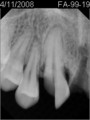

• 9BAC523F-570E-4130-8C4C-56A1CB11D8AD.jpeg

9BAC523F-570E-4130-8C4C-56A1CB11D8AD.jpeg

10.2 KB · Views: 3